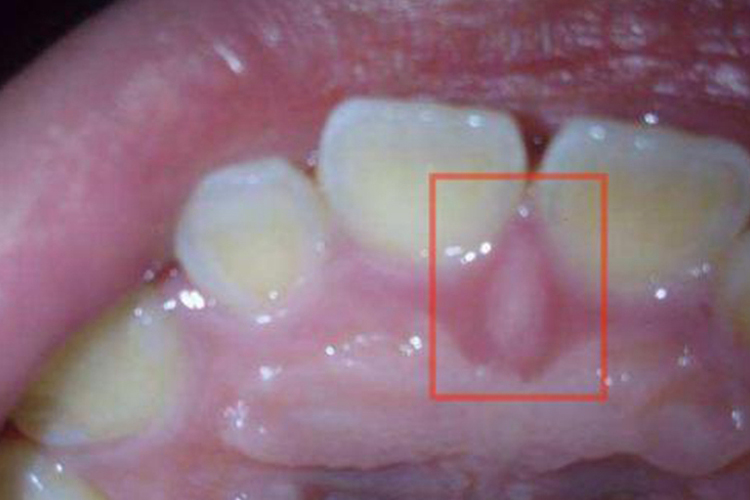

切牙乳突是位于两个中切牙侧的小的软组织突起,其下方为切牙孔,有鼻腭神经和血管通过。

切牙乳突位于上颌腭中缝的前端,上颌中切牙腭侧的卵圆形的软组织突起。下方为切牙孔,有鼻腭神经和血管通过,通常覆盖该区的义齿基托组织面需适当缓冲,以免压迫切牙乳突产生疼痛。

切牙乳突与上颌中切牙之间的距离是相对稳定的,因此在排列上颌全口义齿的中切牙时可以参照切牙乳突来进行。在真牙列时,切牙乳突多位于二中切牙之间和上颌骨的中分线上,所以切牙乳突尖端常用作确定人工牙列的中分线的依据。